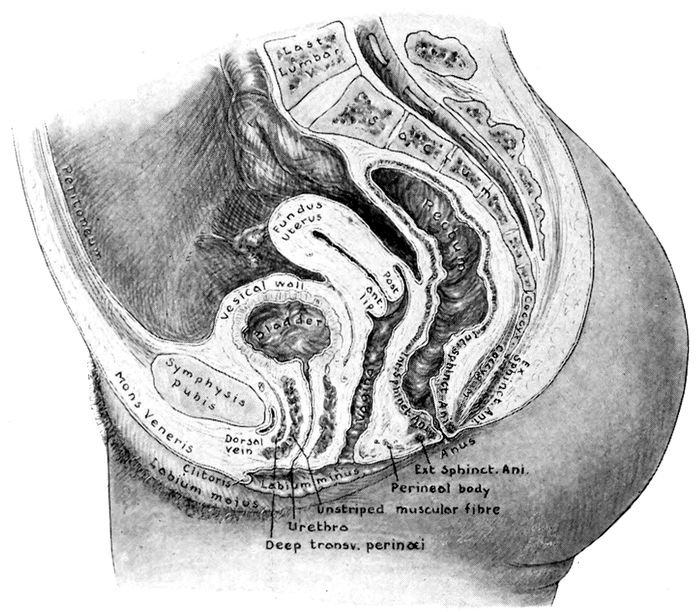

Fig. 3.—Visceral relations. (Redrawn from Gray.)

THE SOFT PARTS

Inside the pelvis are the organs of generation with

their accessory structures and supporting tissues.

21Of first importance are the ovaries, tubes and uterus,

together with the vagina. These special structures are

the true genital organs. They are bounded in front by

the bladder, behind by the rectum, above by the abdominal

viscera, and surrounded everywhere by muscular,

mucous and fatty tissues, which support them and

aid their function.

The Vagina.—The vagina is a hollow organ, about

four inches long, attached to the cervix above and the

vulva below. It is an elastic sheath bounded in front

by the bladder and behind by the rectum. Under normal

conditions, this tube easily admits one or two fingers,

but during labor it dilates enormously to allow the

head to pass. The vagina is lined with a thick mucous

membrane, ridged and roughened by folds, which are

called rugæ. Thus a continuous channel connects the

ovary with the outside and through it pass, at appropriate

times, the ovule, the menstrual blood, the uterine

secretions, the child, the placenta, and the lochia.

The Uterus.—The uterus (womb) is a pear-shaped

organ, flattened from before backward, and composed of

unstriped or involuntary muscle cells and connective

tissue. Normally the virgin uterus measures from two

and one-half to three inches in length, and weighs about

two ounces. It is suspended in the middle of the pelvis

by strong ligaments, so that the fundus inclines gently

forward against the bladder. When the bladder fills,

the uterus is pushed backward. Most of the organ is

internal, but a small part of the lower pole is grasped

by the vagina, in which the lower end with its invaluable

aperture, the os, dips and swings. The part above

the vagina is called the body or fundus, and is covered

with the serous membrane (peritoneum) that lines the

abdominal cavity. Below the fundus is the cervix or

neck, which lies partly above and partly within the

22vagina. The cavity of the uterus is usually closed by

the apposition of the walls. The inner surface is covered

with a peculiar kind of membrane called the endometrium,

which is highly vascular. The uterine cavity

opens into the vagina through the os, which is small

and round in the nulliparous woman, and slit-shaped or

gaping in the woman who has borne a child.